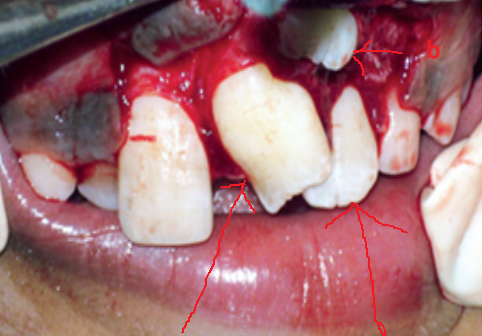

Răng thừa (a) làm R11 (b) bị kẹt không mọc ra được Tạo khoảng trước phẫu thuật

http://www.dentalnews.com/wp-content/uploads/2015/10/Maxillary-Central14.jpg =http://www.dentalnews.com/wp-content/uploads/2015/10/Maxillary-Central16.jpg =

Phẫu thuật lấy răng thừa sau 4 tháng tạo khoảng Chỉnh nha kéo R11 ngầm lên

Qúa trình chỉnh nha kéo răng cửa mọc ngầm hoàn tất

Hình 5: Minh họa phẫu thuật lấy răng thừa kết hợp với chỉnh nha ở một bé trai 9 tuổi